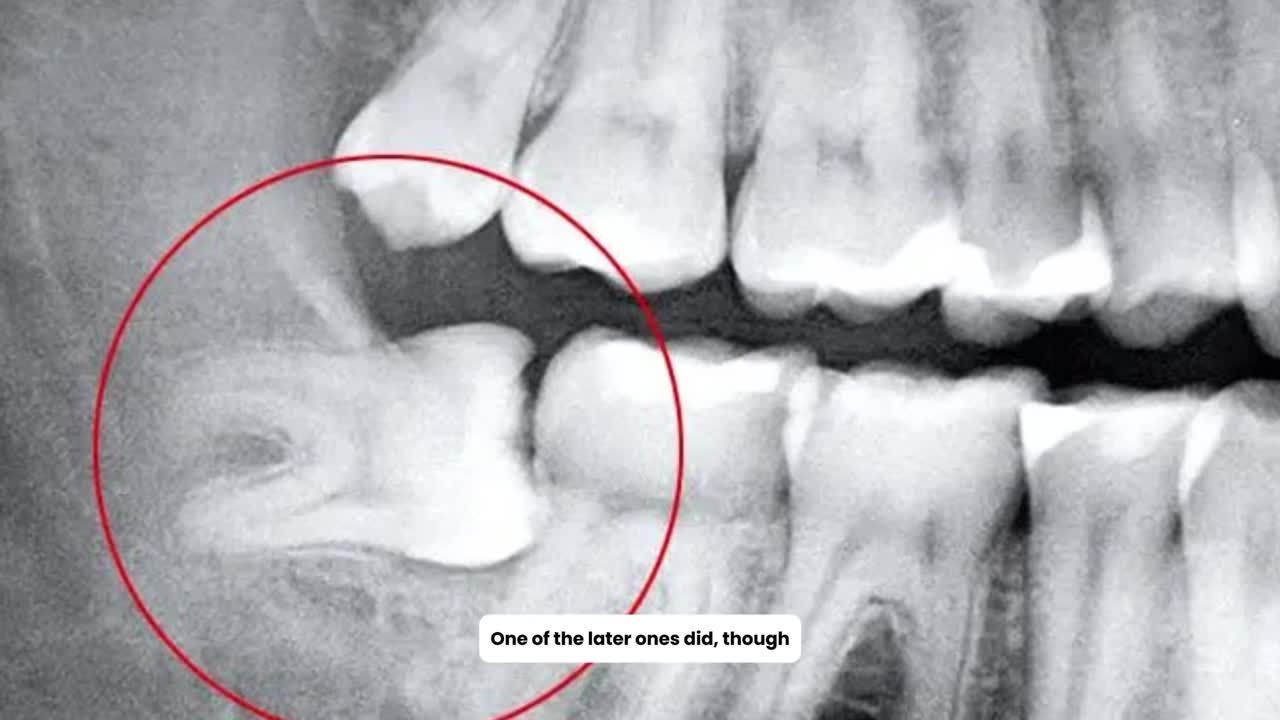

Nhưng nếu răng mọc lệch, mọc ngầm, gây đau nhức hoặc làm hỏng răng bên cạnh, bác sĩ thường khuyên nên nhổ sớm để tránh biến chứng.

Nhổ răng khôn số 38 mọc lệch 45 độ đâm vào răng 7 cho bạn Hiền đang chỉnh nha tại Nha Khoa Thuỳ Anh